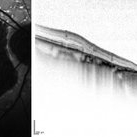

Fundus autofluorescence and SD-OCT of a 70-year-old woman with geographic atrophy sec. to Central areolar choroidal dystrophy